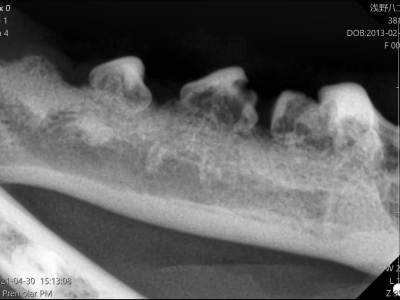

症例(犬1)X線

X線を撮ってみると、歯根は著しく変質し骨との境目が分からなくなっています。